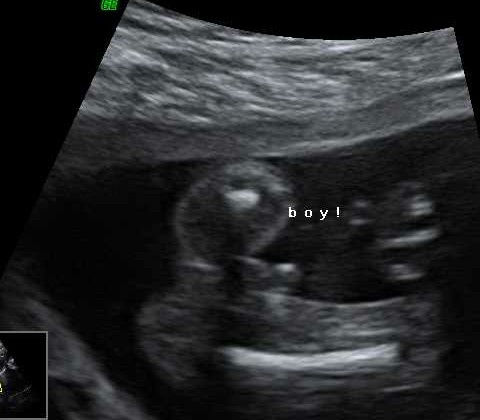

WE ARE TEAM BLUE AND I CRIED SO HARD!! OH thought it was hilarious and took photos... Git 😂 we went shopping after and bought some really cute boy stuff!!

Wasn't expecting much from the 3D peek but my god does nugget look like his dad! 😊😊 it's been a very good day ❤